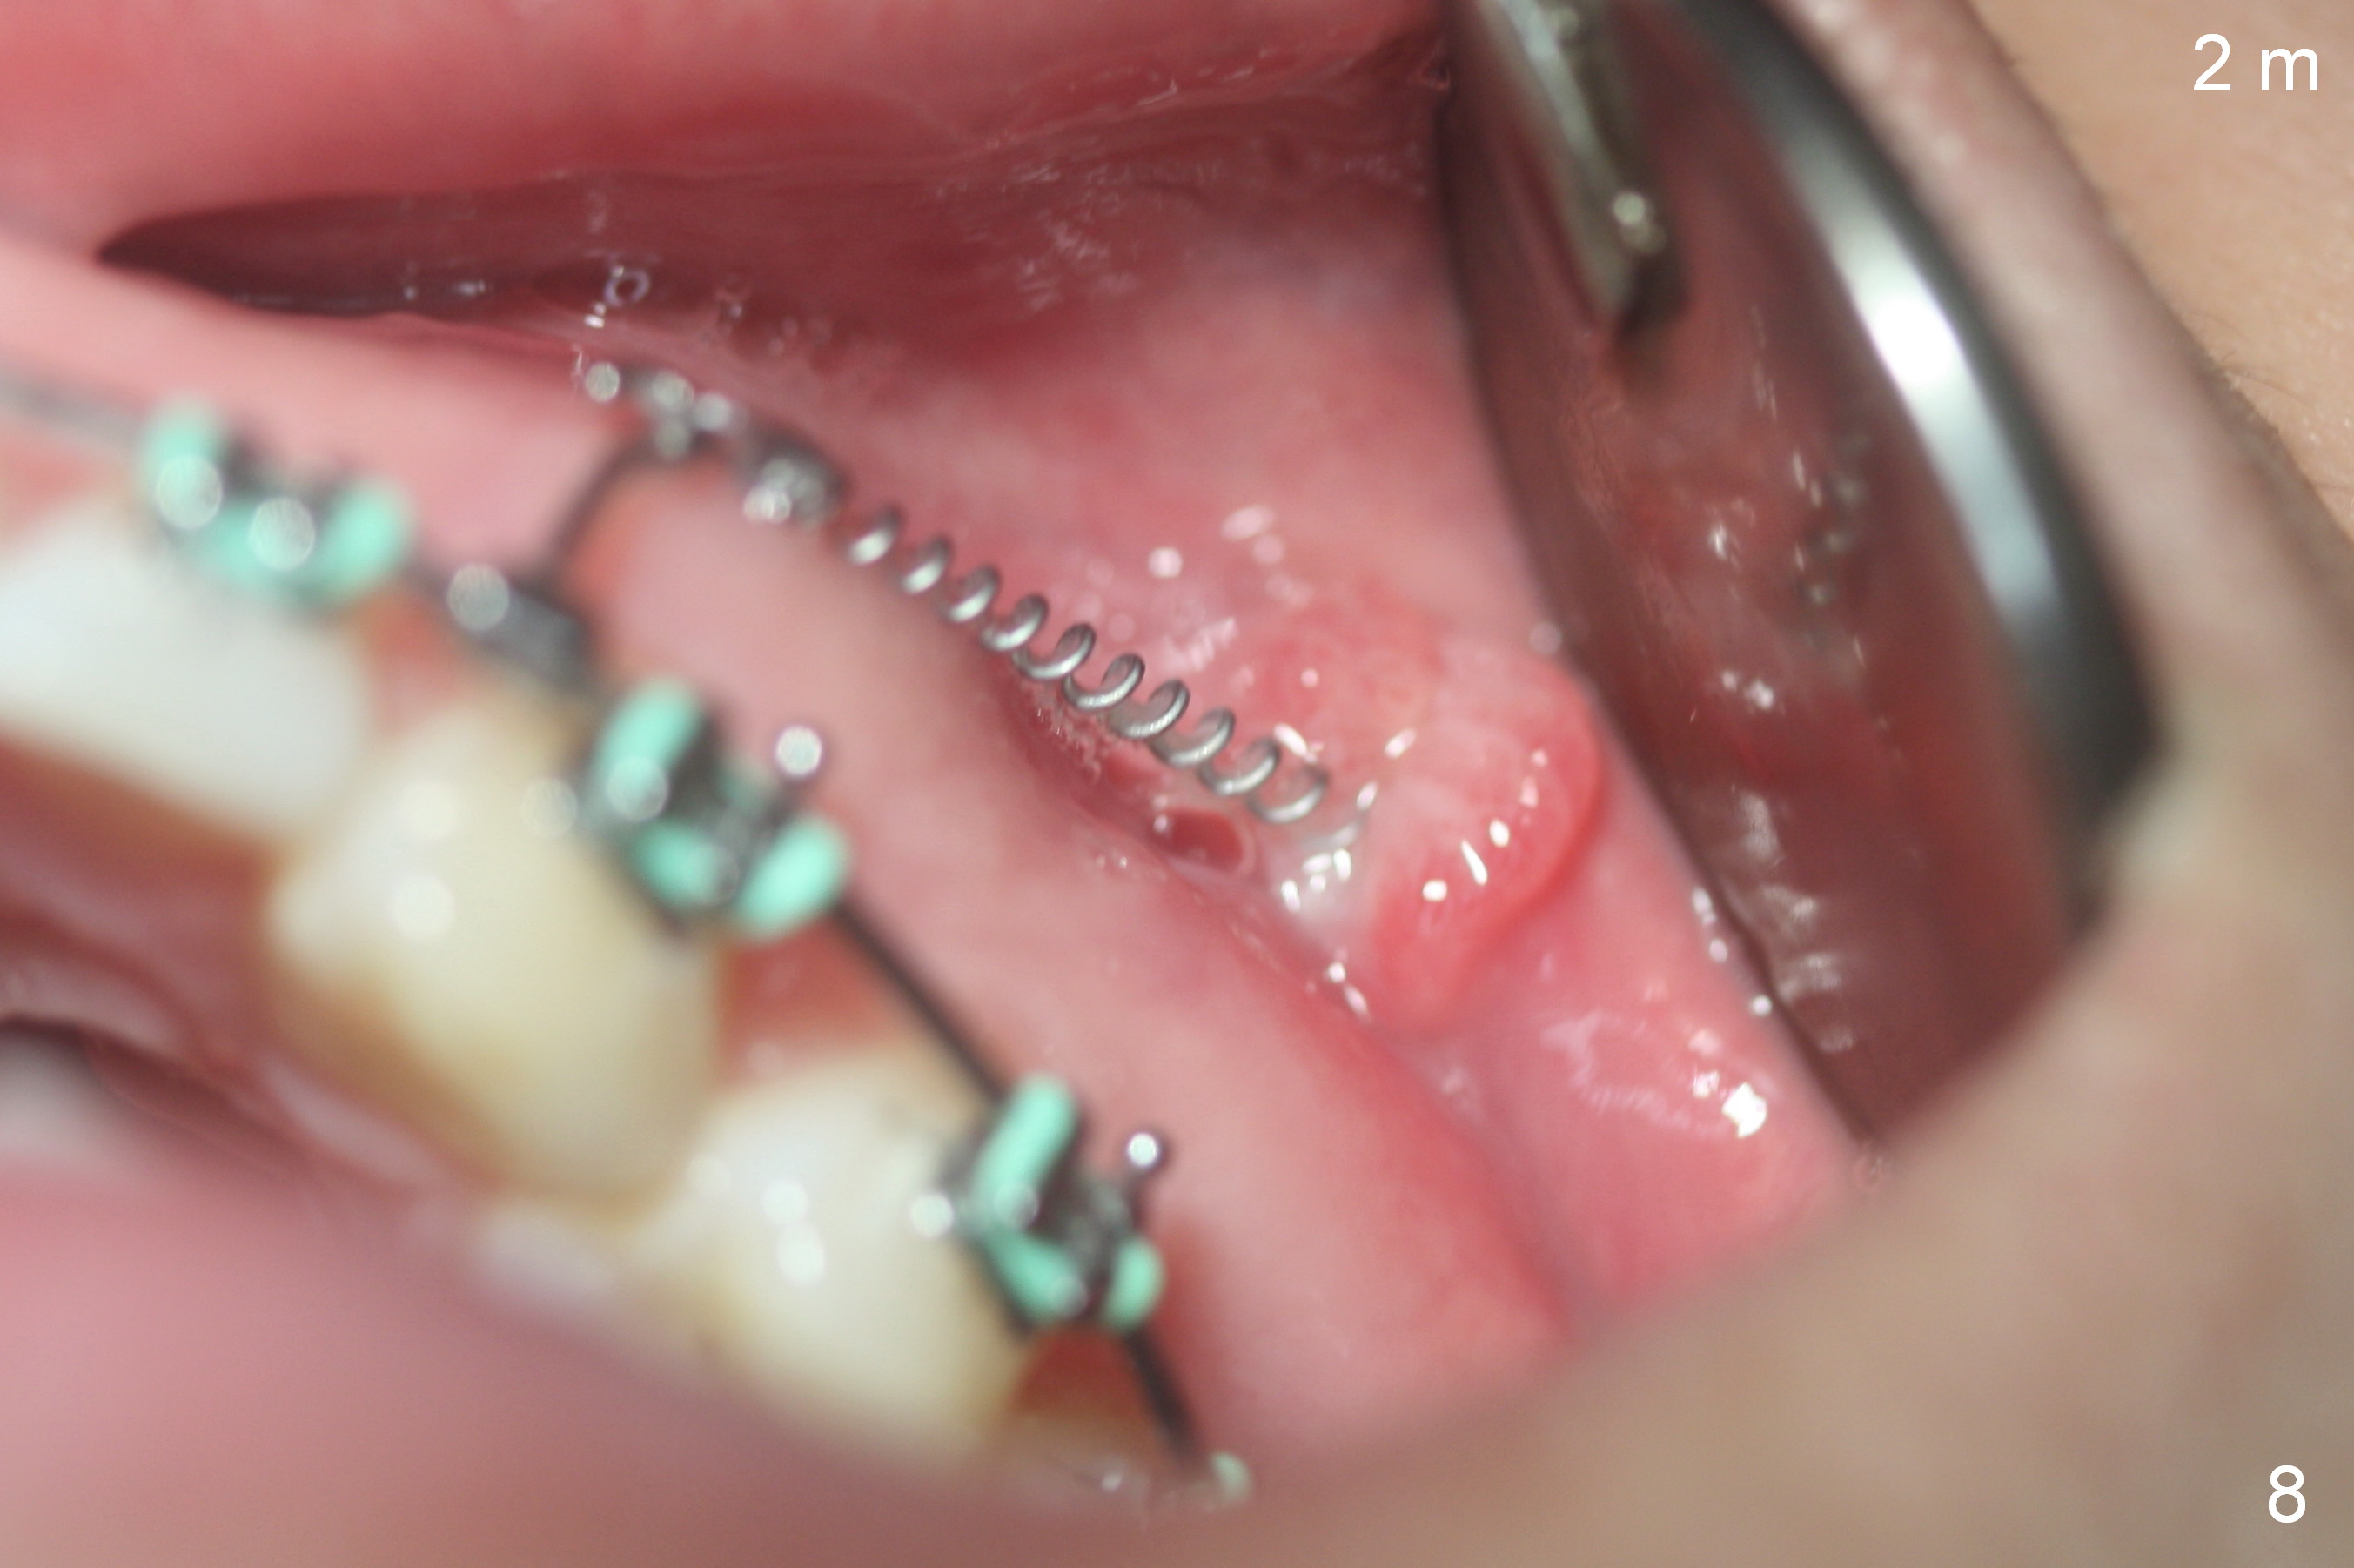

Postop follow up at 1 week (Fig.5,6), 2 months (Fig.7,8) and 3 months (Fig.9,10).  Granulation tissue forms around the entrance of closed coil spring with tenderness 2 months postop (Fig.7,8).  Pain persists especially on the left.  Tension of coiled spring associated with zygomatic implants is low; new coiled springs are added for the posterior implants (Fig.9,10).  Later the left spring associated with the left zygomatic implant fractures.